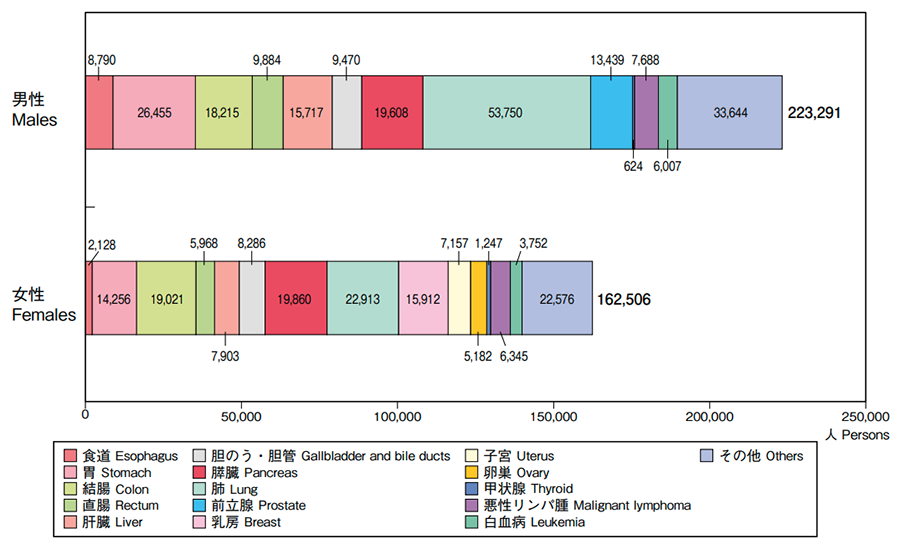

また、同じく2021年のデータによると、がんによる死亡者の数は、約37万8,600人(男性約21万8,900人、女性約15万9,700人)と推計されています。部位別でみると、男性では肺がん(24%)が最も多く、次いで大腸がん(13%)、胃がん(12%)、膵臓がん(8%)、肝臓がん(7%)の順、女性では大腸がん(16%)が最も多く、肺がん(14%)、膵臓がん(12%)、乳がん(10%)、胃がん(9%)と続きます。

部位別のがん死亡者数(2020年)